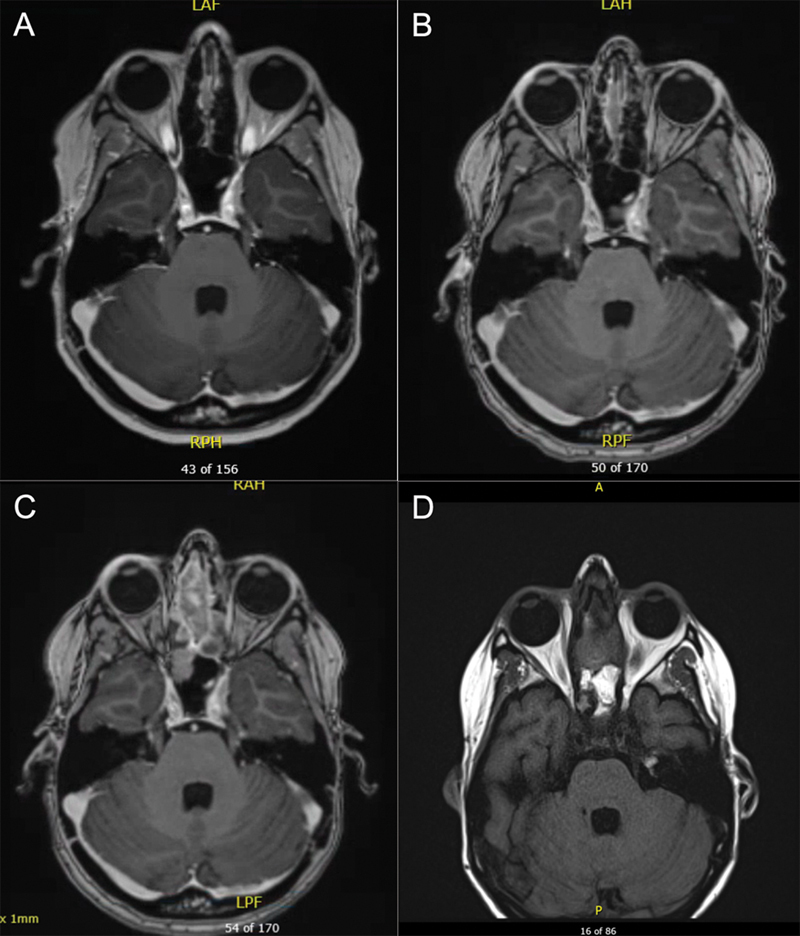

背景 放射治疗是治疗脑肿瘤的主要方法,但延迟并发症包括继发性恶性肿瘤,可能在治疗结束后数月至数年发生。方法 我们回顾了一名 41 岁女性的病历,她因复发性星形细胞瘤接受了 60 Gy 的放射治疗,6 年后又患上了局部晚期鼻窦畸胎肉瘤。我们检索了MEDLINE、Embase和Web of Science,对曾因脑肿瘤接受过头颅照射的患者中经活检证实的鼻窦恶性肿瘤进行了范围界定。结果 据我们所知,这是首例因脑瘤接受颅内照射后出现鼻窦畸胎肉瘤的患者报告。我们对 1907 项研究进行了范围审查,发现了 14 例类似的继发性鼻窦恶性肿瘤病例。原发癌诊断的中位年龄为 39.5 岁(标准差 [SD]:21.9),中位放射剂量为 54 Gy(标准差:20.3)。原发性癌症与继发性鼻窦癌之间的中位潜伏期为 9.5 年(标准差:5.8)。嗅神经母细胞瘤是最常见的鼻窦癌(4 例)。50%的患者在1.5年内死于鼻窦癌。结论 因治疗原发性脑肿瘤而接受鼻窦部位放射线照射(包括低剂量或散射辐射)的患者可能会面临日后罹患继发性鼻窦恶性肿瘤的风险。监测高危患者的医生必须对可能提示鼻窦恶性肿瘤的症状保持警惕,监测工作应包括对整个照射区域进行放射学检查,并仔细观察是否存在继发性恶性肿瘤。

Background  Radiation therapy is a mainstay of treatment for brain tumors, but delayed complications include secondary malignancy which may occur months to years after treatment completion. Methods  We reviewed the medical records of a 41-year-old female treated with 60 Gy of radiation for a recurrent astrocytoma, who 6 years later developed a locally advanced sinonasal teratocarcinosarcoma. We searched MEDLINE, Embase, and Web of Science to conduct a scoping review of biopsy-proven sinonasal malignancy in patients who previously received cranial irradiation for a brain tumor. Results  To our knowledge, this is the first report of a patient to present with a sinonasal teratocarcinosarcoma after receiving irradiation for a brain tumor. Our scoping review of 1,907 studies produced 14 similar cases of secondary sinonasal malignancy. Median age of primary cancer diagnosis was 39.5 years old (standard deviation [SD]: 21.9), and median radiation dose was 54 Gy (SD: 20.3). Median latency time between the primary cancer and secondary sinonasal cancer was 9.5 years (SD: 5.8). Olfactory neuroblastoma was the most common sinonasal cancer ( n  = 4). Fifty percent of patients died from their sinonasal cancer within 1.5 years. Conclusion  Patients who receive radiation exposure to the sinonasal region for treatment of a primary brain tumor, including low doses or scatter radiation, may be at risk of a secondary sinonasal malignancy later in life. Physicians who monitor at-risk patients must be vigilant of symptoms which may suggest sinonasal malignancy, and surveillance should include radiographic review with careful monitoring for a secondary malignancy throughout the entire irradiated field.